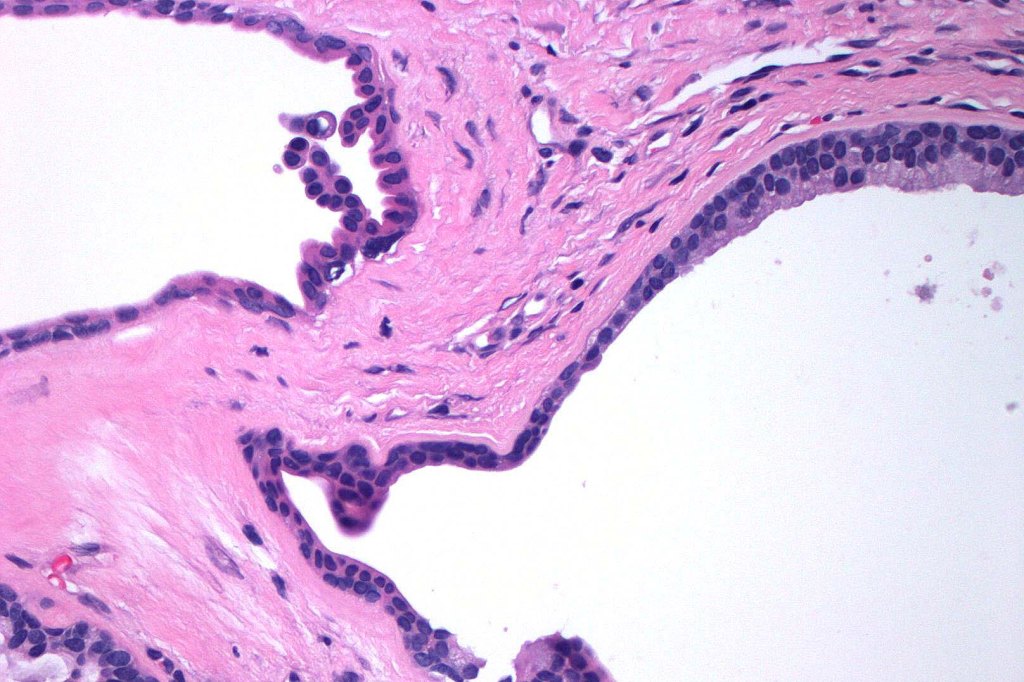

Histological features

•Pseudo-encapsulated unilocular or multilocular

•Outer myoepithelial cells & inner layer of columnar cells with eosinophilic cytoplasm showing decapitation secretion